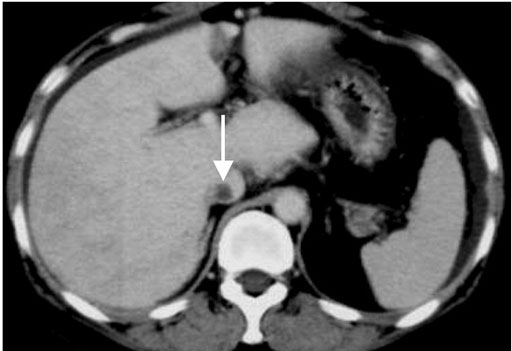

肝静脈は狭小化し、肝実質相であるにもかかわらず、肝静脈は造影されていない(黒矢印)

下大静脈内に血栓が同定される(白矢印)